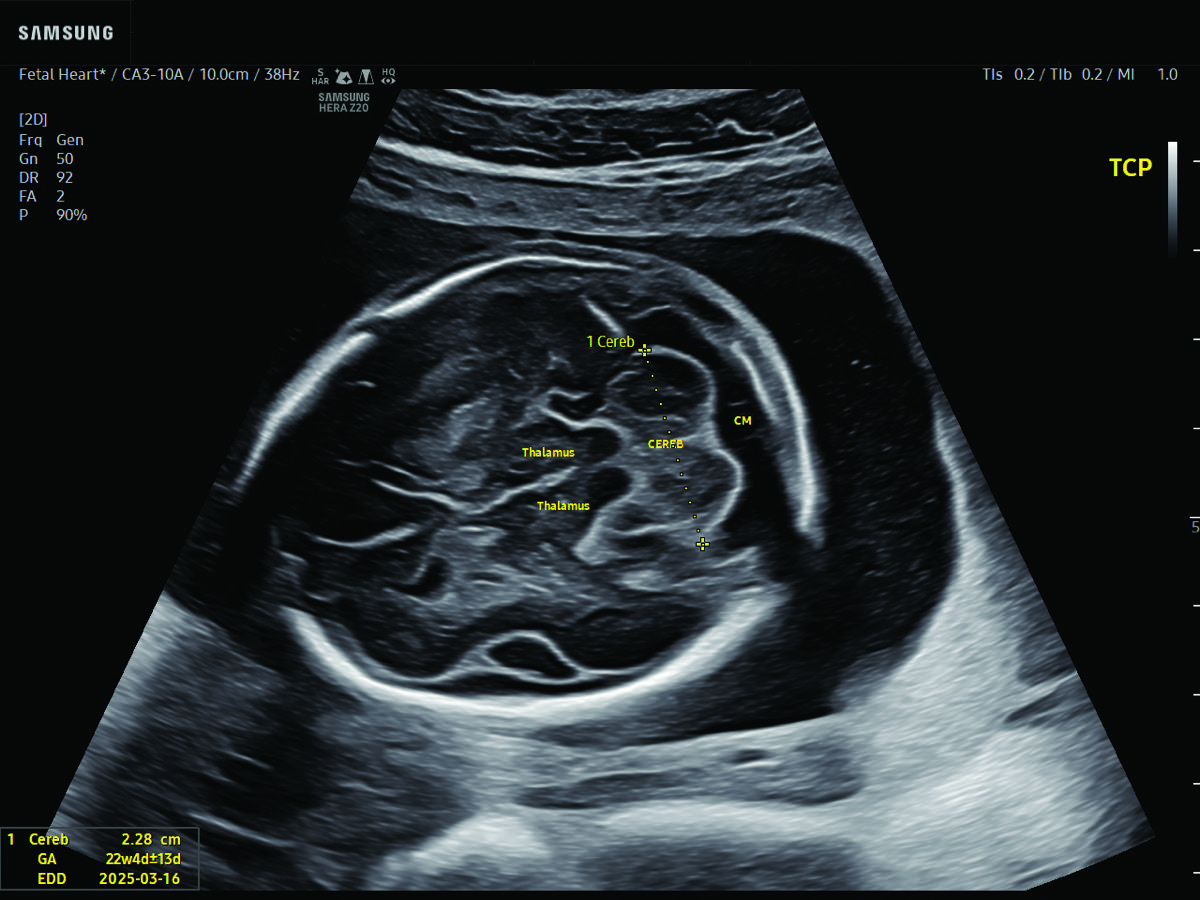

Comprehensive, advanced and expert MFM care for high-risk pregnancies

- Fetal anomalies